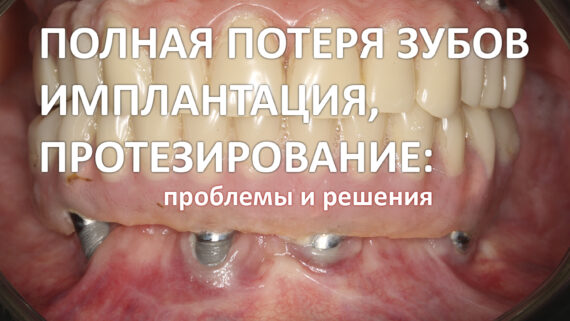

На нижнем фото: контрольный осмотр пациента через 2 месяца после окончательного протезирования.

Через два с половиной месяца картинка выглядит следующим образом:

Брекеты с верхней челюсти уже сняли — ортодонтическое лечение заняло, примерно, 7-8 месяцев. На мой взгляд, достигнут вполне приемлемый результат.

Десна в области нижних резцов приобрела нормальный цвет. Пациент вовсю пользуется новыми зубами, несмотря на то, что коронки временные.

Мы можем приступать к изготовлению постоянных протезов на импланты.

И, на мой взгляд, ортопеду это удалось:

и еще:

На мой взгляд, получилось очень круто. Вернитесь к первой фотографии и посмотрите, с чего мы начали наше лечение.